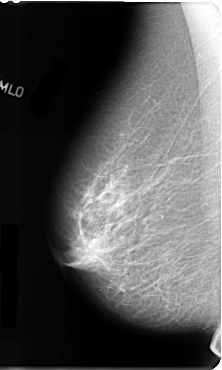

B_3100_1.RIGHT_MLO

LEFT_MLO LINES 4808 PIXELS_PER_LINE 2936 BITS_PER_PIXEL 12 RESOLUTION 50 OVERLAY

FILE: B_3100_1.LEFT_MLO.OVERLAY

TOTAL_ABNORMALITIES 1

ABNORMALITY 1

LESION_TYPE MASS SHAPE IRREGULAR MARGINS OBSCURED-ILL_DEFINED

ASSESSMENT 3

SUBTLETY 2

PATHOLOGY BENIGN

TOTAL_OUTLINES 1

BOUNDARY